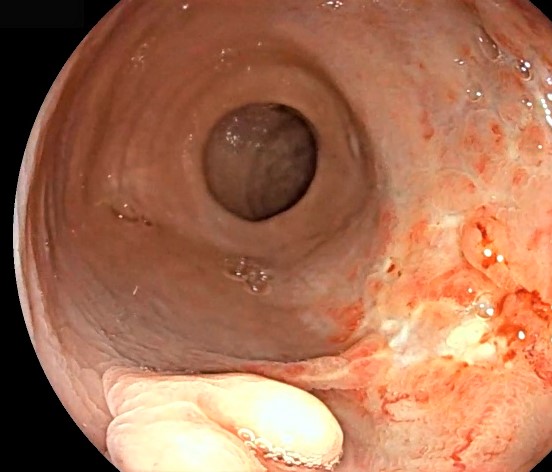

La proctitis por radiación es una complicación común de la radioterapia para tumores malignos pélvicos. Se clasifica en aguda y crónica según el tiempo de aparición de los síntomas.

La proctitis crónica se desarrolla varios meses después de la radioterapia y se caracteriza por formación de neovasos. Si es intensa, pueden incluso aparecer pequeñas úlceras. En estos casos, aparecen síntomas como sangrado rectal, tenesmo y dolor rectal.

El tratamiento suele ser endoscópico, mediante coagulación con plasma de argón (APC), que es una técnica eficaz y segura para el control del sangrado.